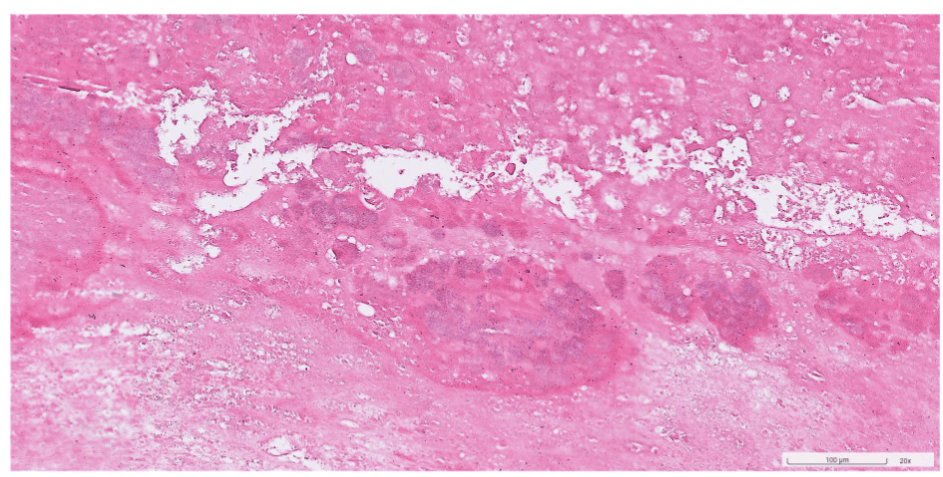

colon cancer